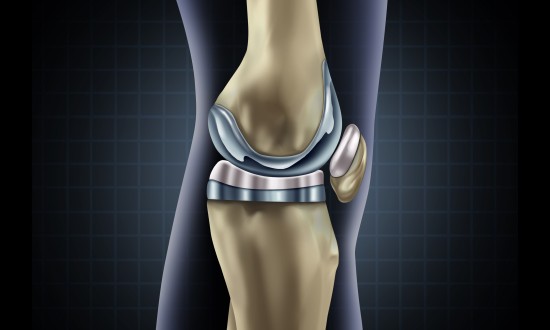

骨科植入器材是指被植入人体内,用于取代、修复、补充、填充或辅助治疗受损伤骨骼的器材的统称。它们主要由金属材料、生物陶瓷材料、高分子材料等制成,可以长期植入人体,对人体的生命和健康有着重大影响。骨科植入......

骨科植入医疗器械,指的是通过手术植入人体,可以起到替代、支撑人体骨骼或者可以定位修复骨骼、关节、软骨等组织的器材材料,主要包括骨接合植入物及关节植入物,如接骨板、接骨螺钉、髓内钉、脊柱内固定植入物、人......